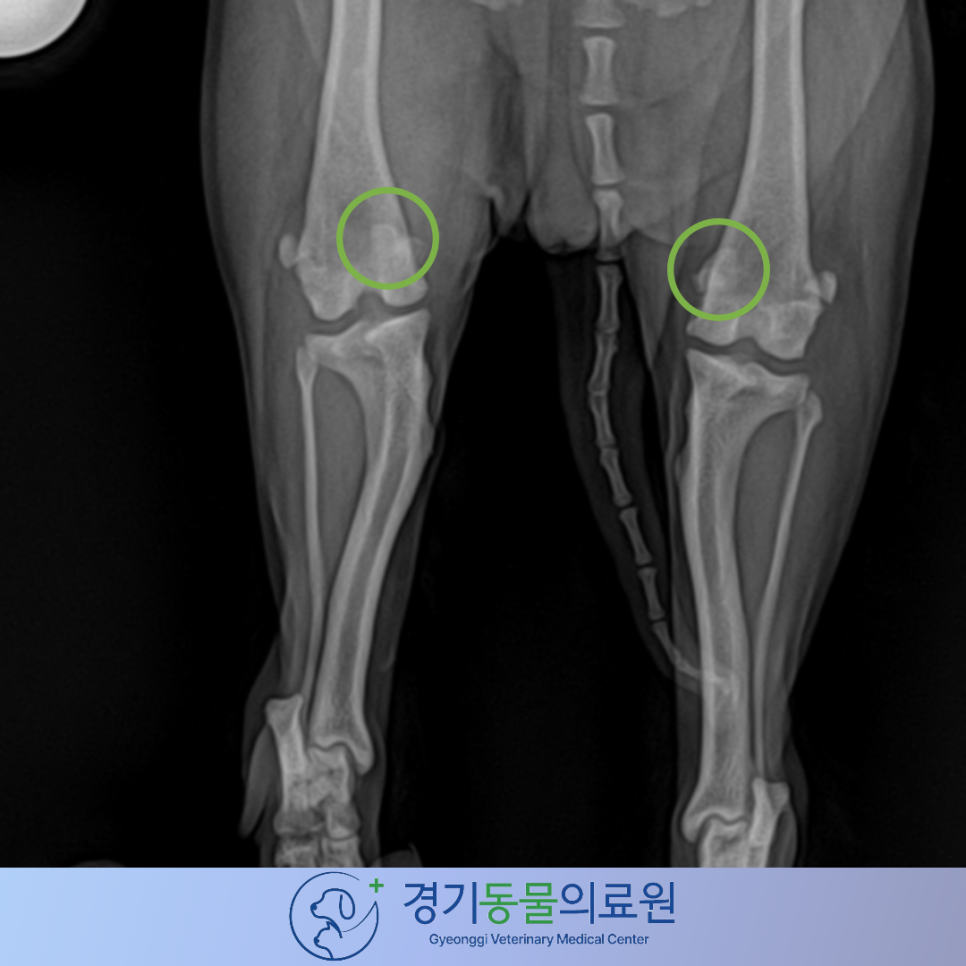

방사선 사진 및 꼼꼼한 신체검사 상에서 양측 슬개골 탈구를 확인하였습니다.

▶ 수술 전 방사선 검사

방사선 검사 상에서 양측의 내측 슬개골탈구(초록색 동그라미)가 확인되었습니다.